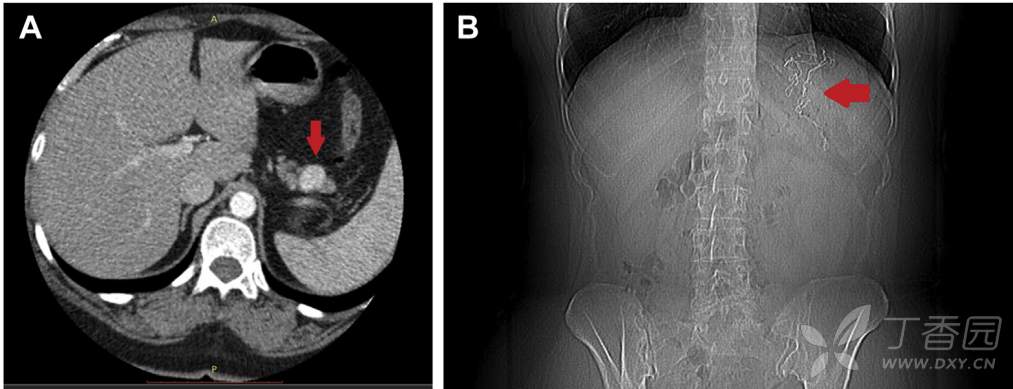

一名45岁女性因子宫肿瘤及胰尾神经内分泌肿瘤(图A)而行腹盆腔手术。

术后患者出现恶心、呕吐、食欲减退、乏力及发热,病情逐渐加重。术后2月腹部CT提示胰瘘及左侧腹壁局限性脓肿,遂给予针对性治疗。但患者全身情况进一步恶化,出现上腹痛、恶心呕吐、食欲减退及体重下降(超过30Kg)。6个月后复查CT提示胃内幽门前区团块状物质,内含高密度线状影(图B,C)。